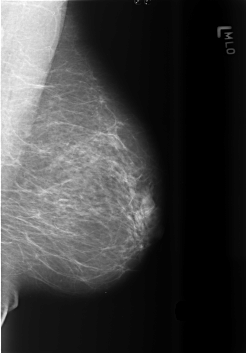

B_3432_1.LEFT_MLO

B_3432_1.LEFT_CC

LEFT_CC LINES 5584 PIXELS_PER_LINE 3960 BITS_PER_PIXEL 12 RESOLUTION 50 NON_OVERLAY

LEFT_MLO LINES 5648 PIXELS_PER_LINE 3928 BITS_PER_PIXEL 12 RESOLUTION 50 NON_OVERLAY